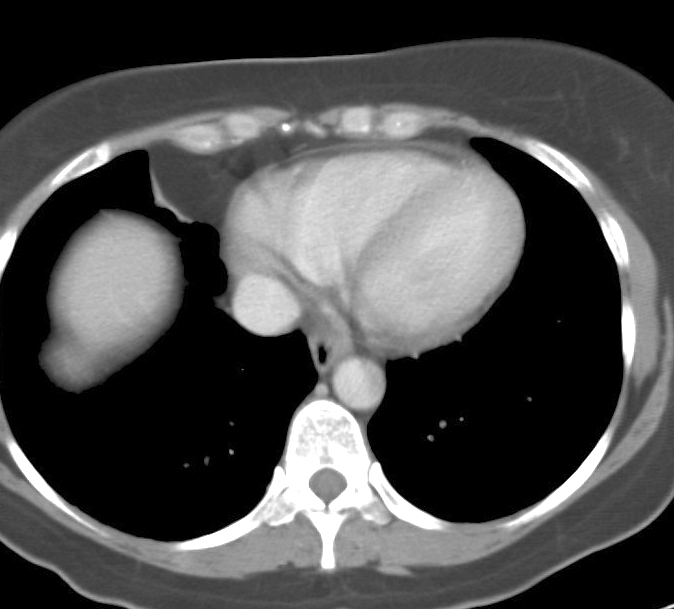

Fat Pad

Case 11b